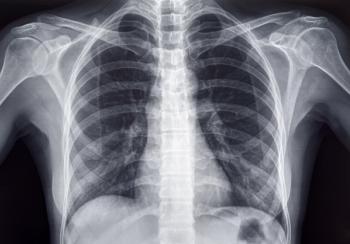

Missed Follow-up Appointments Linked to Worse Survival in Stage 1 Lung Cancer Patients

A recent study highlights a concerning association between missed follow-up appointments and an increased risk of death in people diagnosed with stage I non-small cell lung cancer.

The analysis included adults diagnosed with stage I non-small cell lung cancer at the Indiana University hospital network between 2007 and 2016. The study excluded patients whose records were missing demographic information or had only one appointment scheduled, and those who did not survive for at least one year following diagnosis. The researchers defined a missed appointment as an unattended follow-up visit within a year after diagnosis without an attended appointment within the next 60 days.